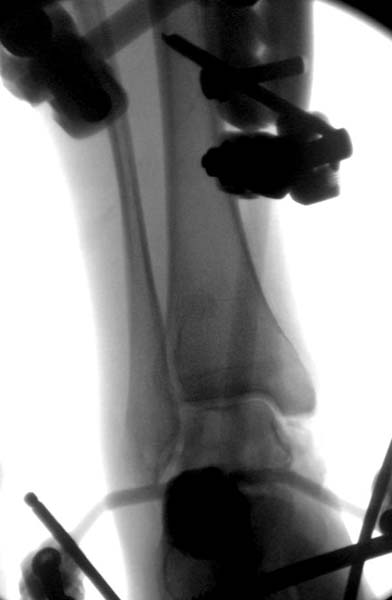

После спадения отека на стопе произведена фиксация тарана. Кстати, коллеги пересмотрели первоначальную консультацию по позвоночнику и на двух уровнях провели фиксацию. Из-за длительного постельного режима без нагрузки таз не стали оперировать...